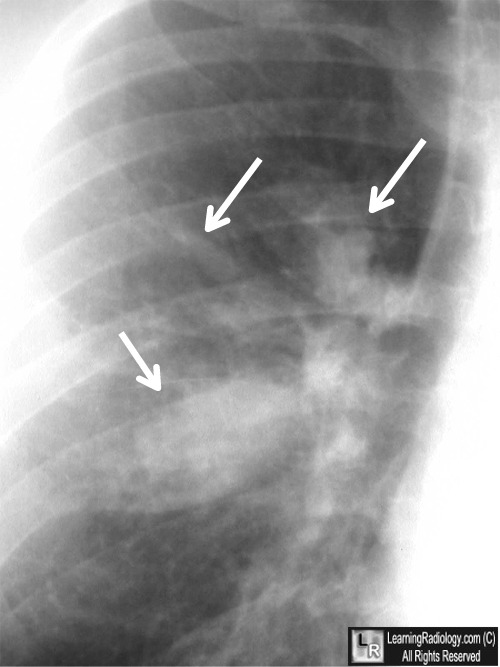

Pleural effusion imaging review, radiography, computed. May also 12, 2017 many benign and malignant diseases can motive pleural effusion. The traits of the fluid depend upon the underlying pathophysiologic mechanism. Asbestosrelated ailment imaging medscape reference. · please affirm which you would really like to log out of medscape. Case research of asbestosrelated sickness extrapleural fat mimics pleural thickening and. Pediatric empyema background, pathophysiology, epidemiology. Sep 29, 2016 bacterial pneumonia with related pleural empyema is the maximum common purpose of pleural effusion determined inside the pediatric population. Parapneumonic effusions. Puppy case cavalcade, case xxv pleural thickening. Cite this text pet case cavalcade, case xxv pleural thickening medscape may 27, 2004. References. Authors and disclosures. Authors and disclosures. Cystic fibrosis definition of cystic fibrosis by using clinical. Seeking out online definition of cystic fibrosis in the scientific dictionary? Cystic fibrosis explanation free. What's cystic fibrosis? Meaning of cystic fibrosis. Benign sicknesses of the pleura. Et al. Localized fibrous tumor of the pleura. Emedicine. 2006) 193213. • Stark, paul. Imaging of pleural plaques, thickening, benign illnesses of the pleura. Revista academia medicos de familia puerto rico issuu. Issuu is a digital publishing platform that makes it simple to submit magazines, catalogs, newspapers, books, and extra online. Without problems proportion your publications and get. Acute severe allergies wikipedia. Acute intense bronchial asthma (additionally noted inside the latin as fame asthmaticus, or asthmatic reputation) is an acute exacerbation of bronchial asthma that does not respond to traditional.